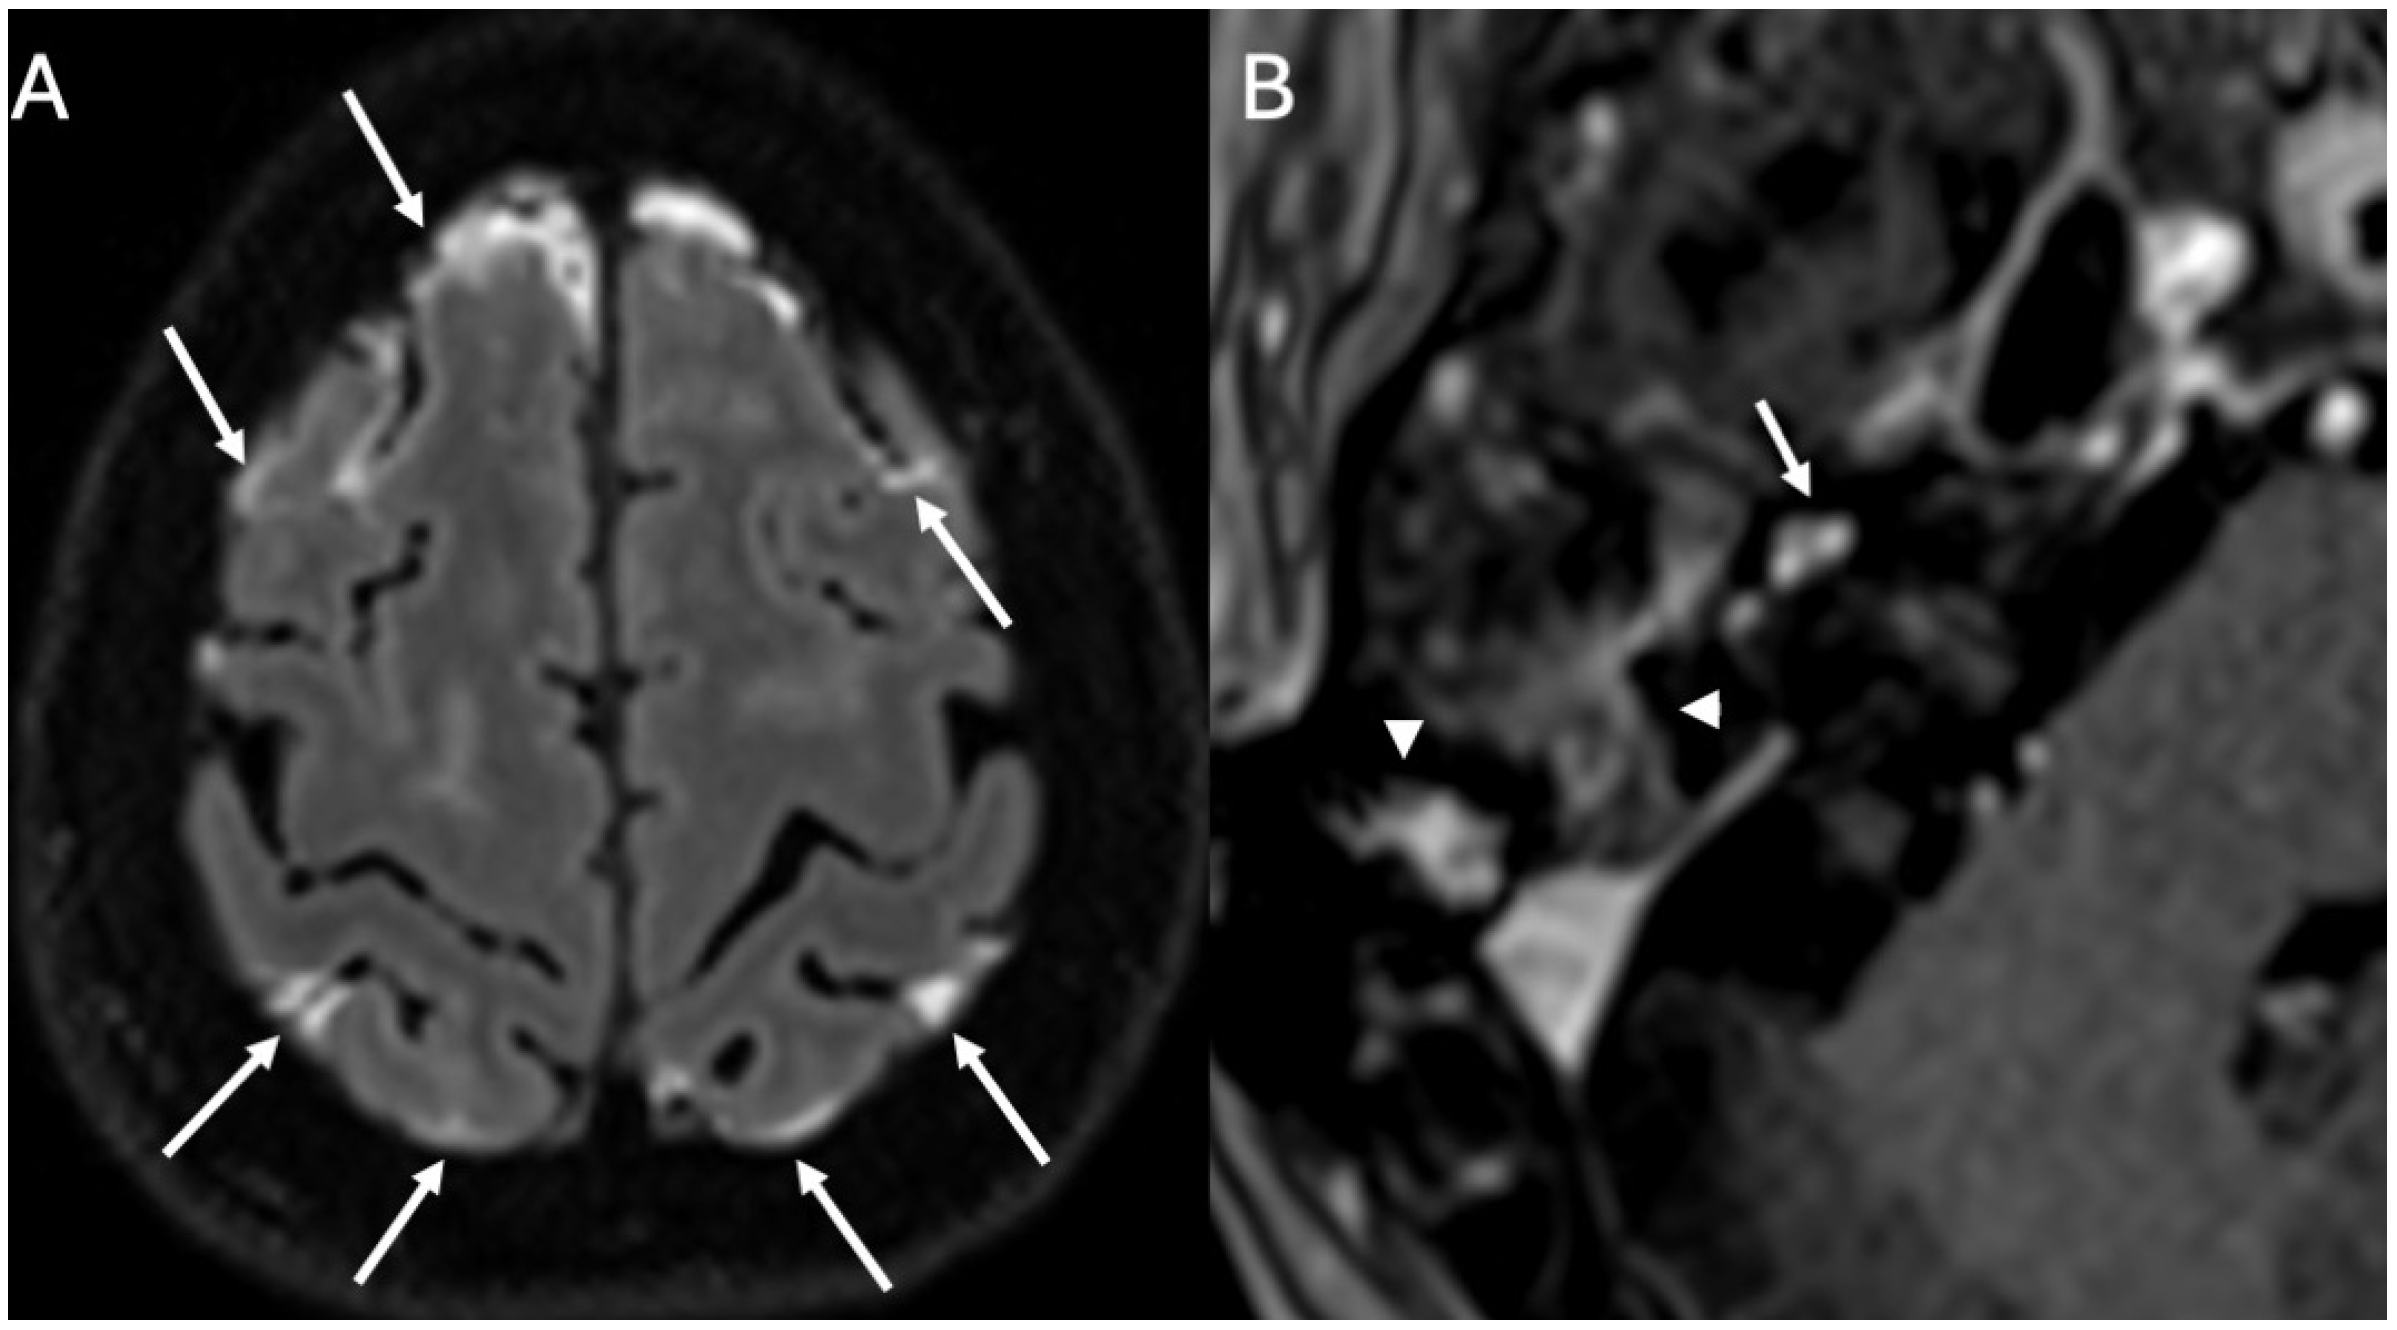

3.4. Labyrinthitis and Vestibulocochlear Neuritis

Imaging

3.5. Cochlear Hemorrhage